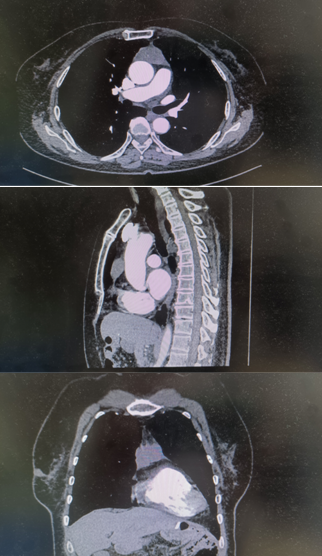

胸部ct提示:前纵隔肿块,增强扫描后考虑胸腺瘤

纵隔肿物不但占据了胸腔很大空间,压迫并影响了周围的正常肺组织功能,还与心包、主动脉、无名静脉、肺动静脉关系密切,手术难度和风险很大;一旦升主动脉及无名静脉出血,后果不堪设想。但为了尽快解决王阿姨的痛苦,市三院心胸外科杨锋副主任医师团队经过术前全科讨论,详细制定手术方案,决定为患者实施剑突下腔镜三孔式纵隔肿瘤切除术。